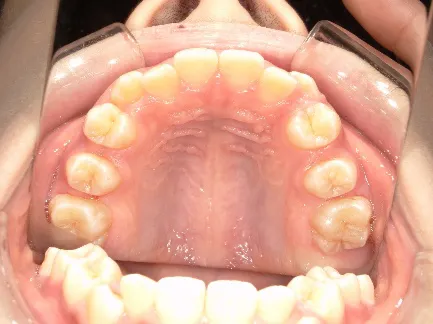

*マルチブラケット法移行後

治療中④中1:治療中 マルチブラケット法へ移行